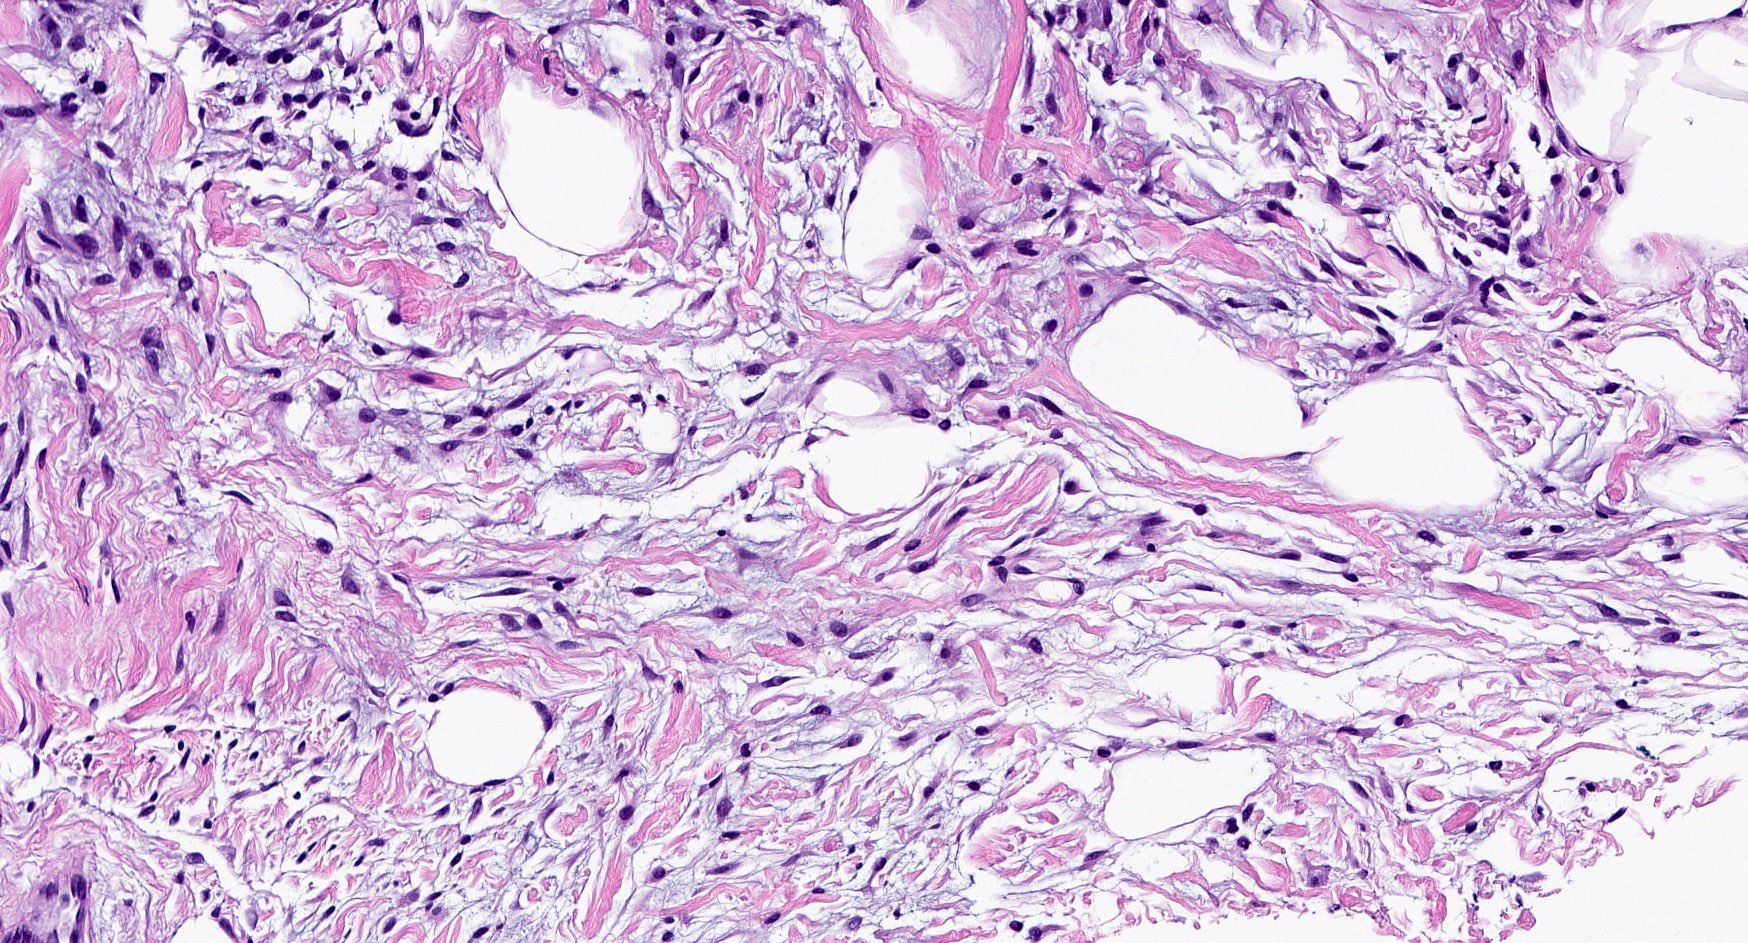

Microscopic (histologic) images

- Bland, uniform, short to elongated spindle cells arranged as short haphazard intersecting fascicles admixed with bands of hyalinized, brightly eosinophilic collagen and variable amounts of fat

- Focal myxoid stromal changes common

- Collagenized / fibrous: collagenous stroma predominates, may have hypocellular myofibroblastic spindle cell component

- Myxoid: stellate and spindle cells in abundant myxoid stroma (Histol Histopathol 2016;31:1)